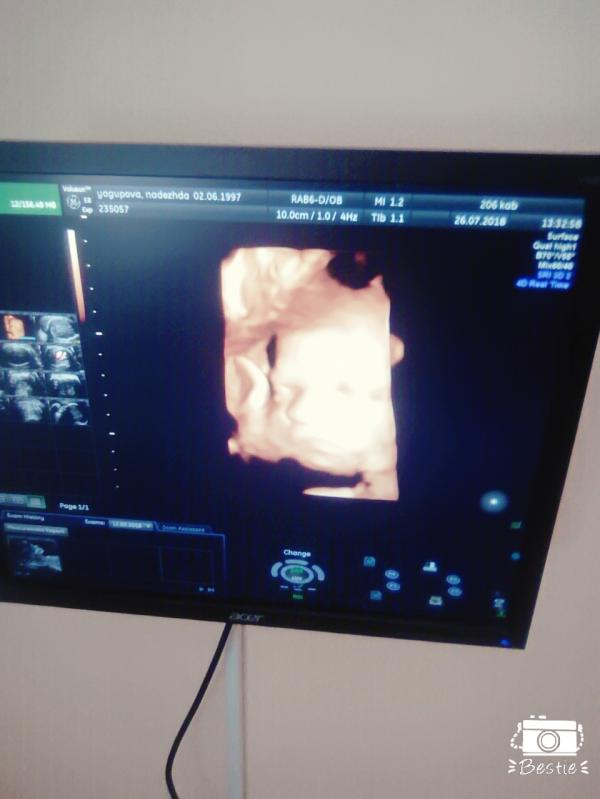

Сегодня на УЗИ была, подтвердили мальчика!!

Не верится что уже почти 32 недели